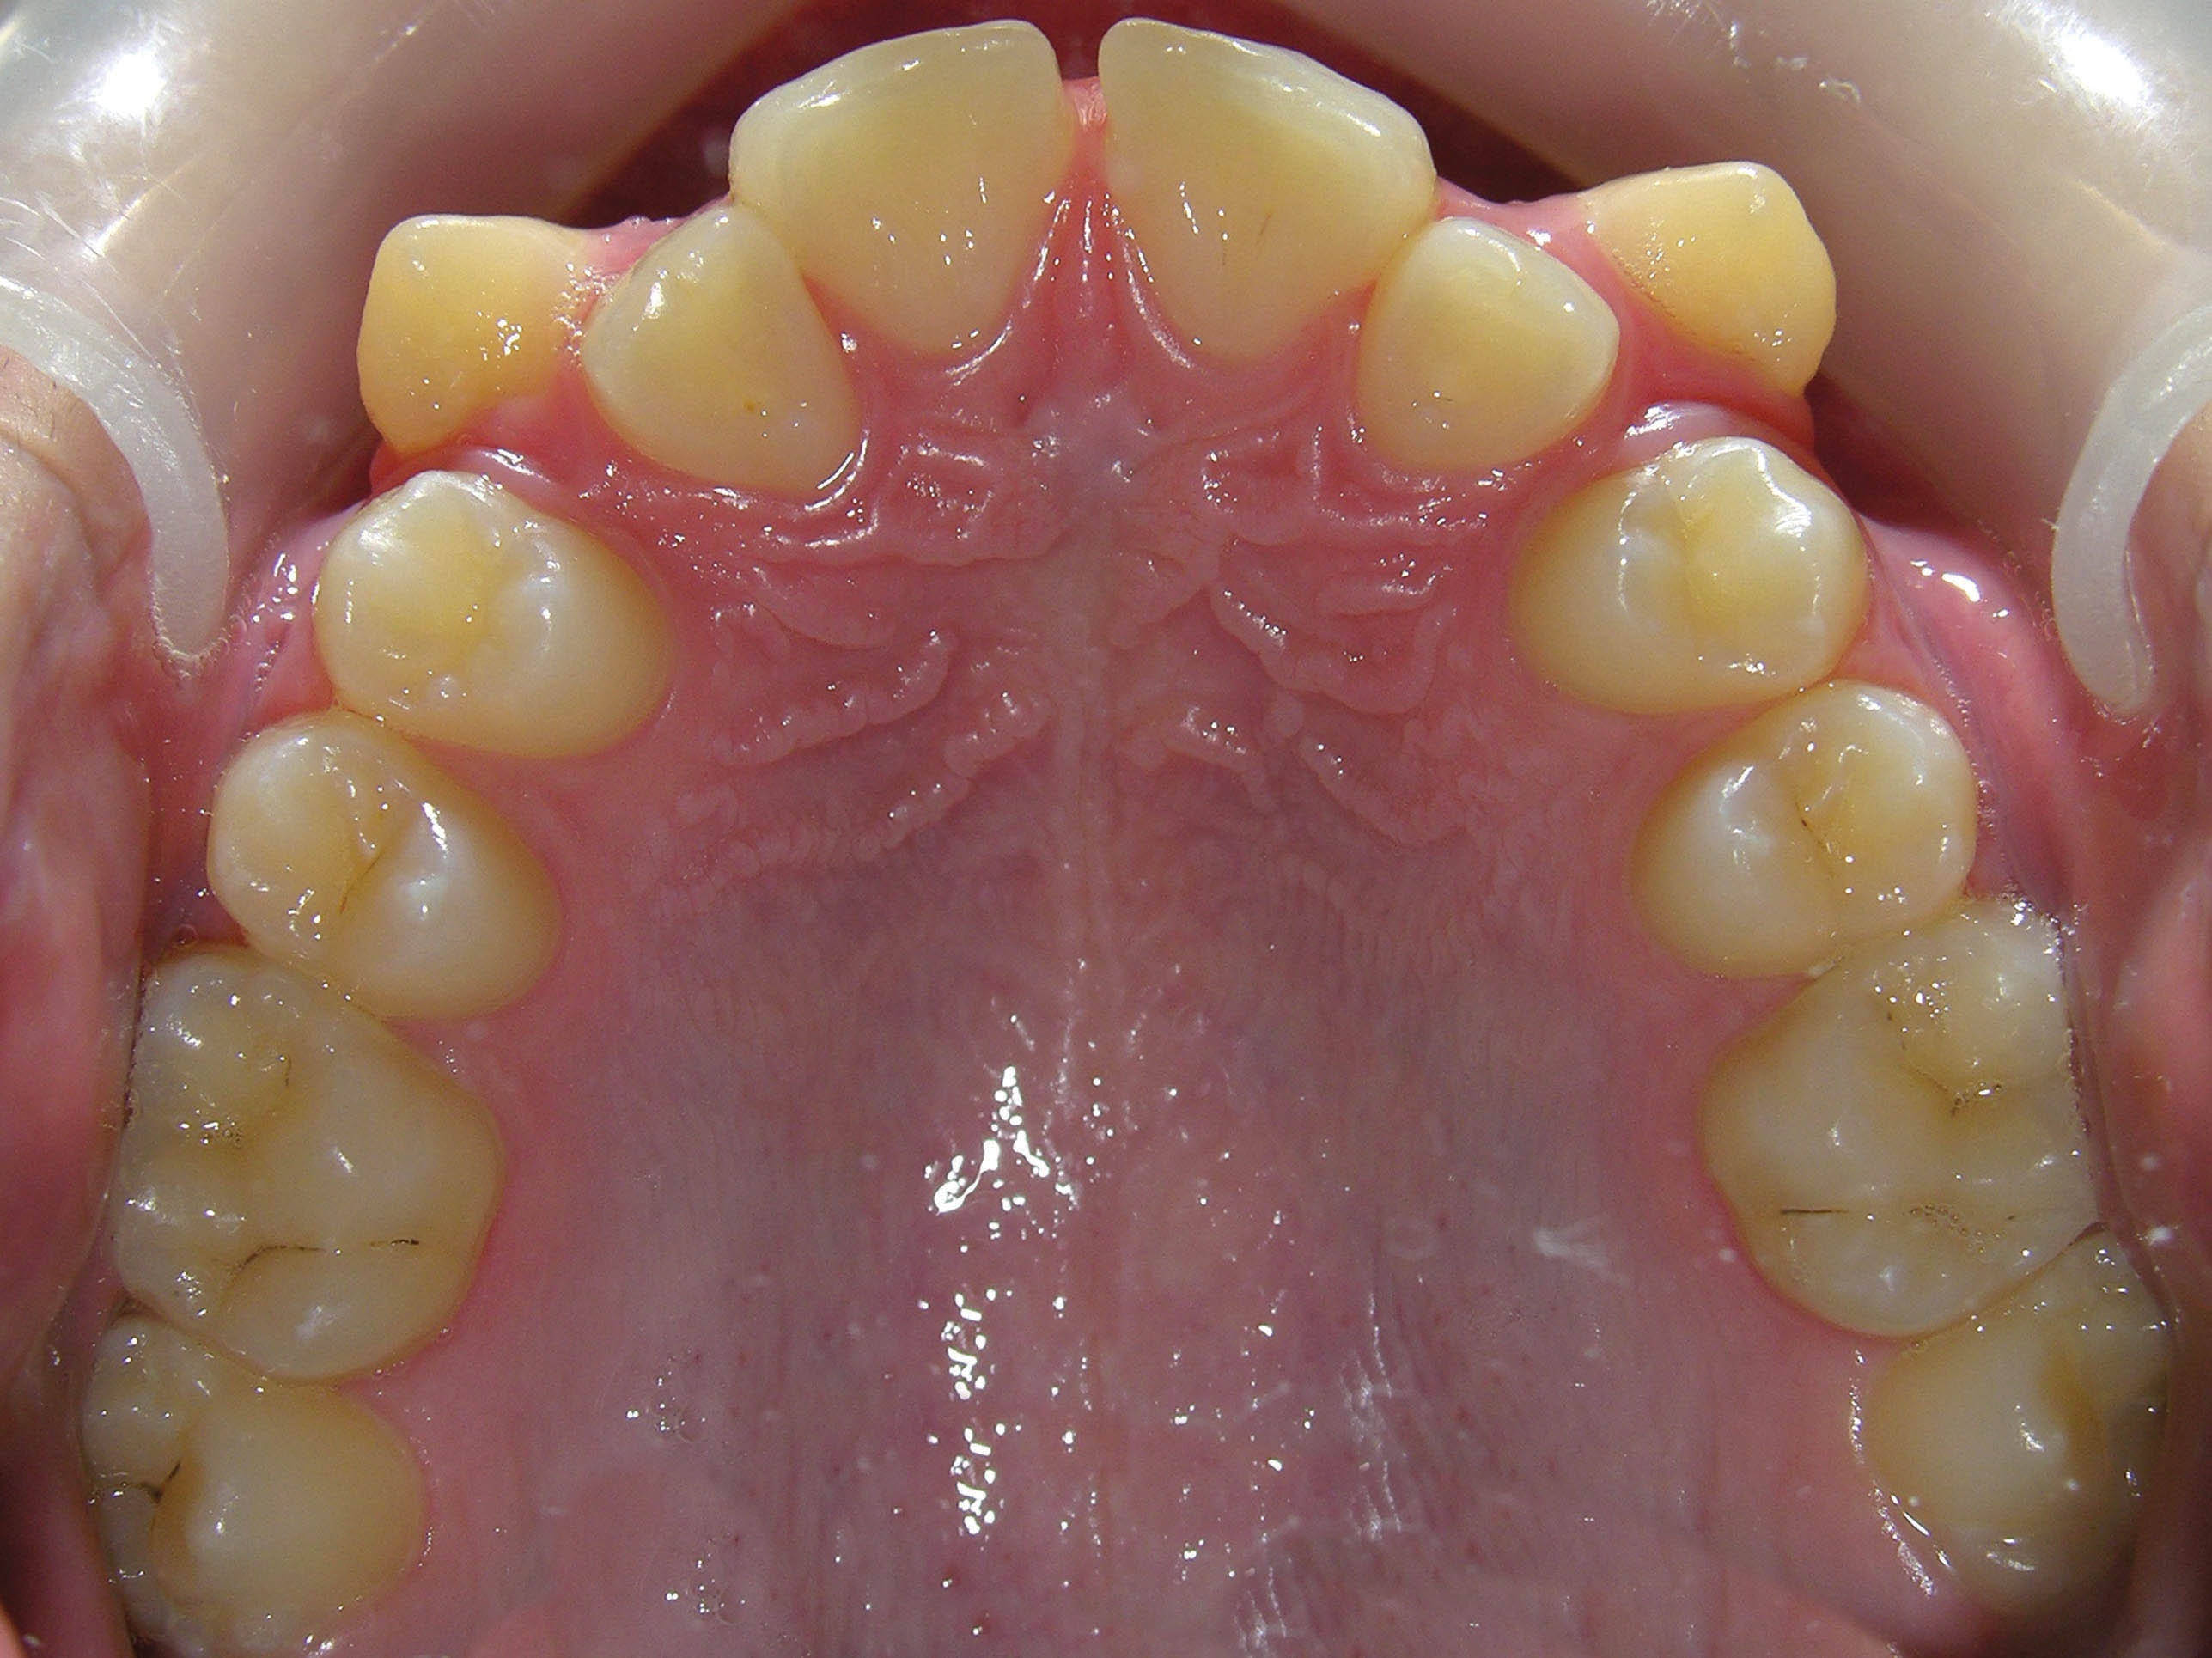

قبل از درمان